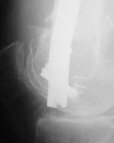

A. Difficult reductions, even in retrograde nailing (my preference, easier control of "small" distal fragment) and it is much, much harder to do it anterograde (Alex, do you have one good case in your collection of anterograde nailing in very distal fractures - as you have suggested that I

Malpositioning is much too common (recurvatum, varus - valgus).

B. Fixation loosening: distal cutting of the nail, non-unions do happen (cases attached).